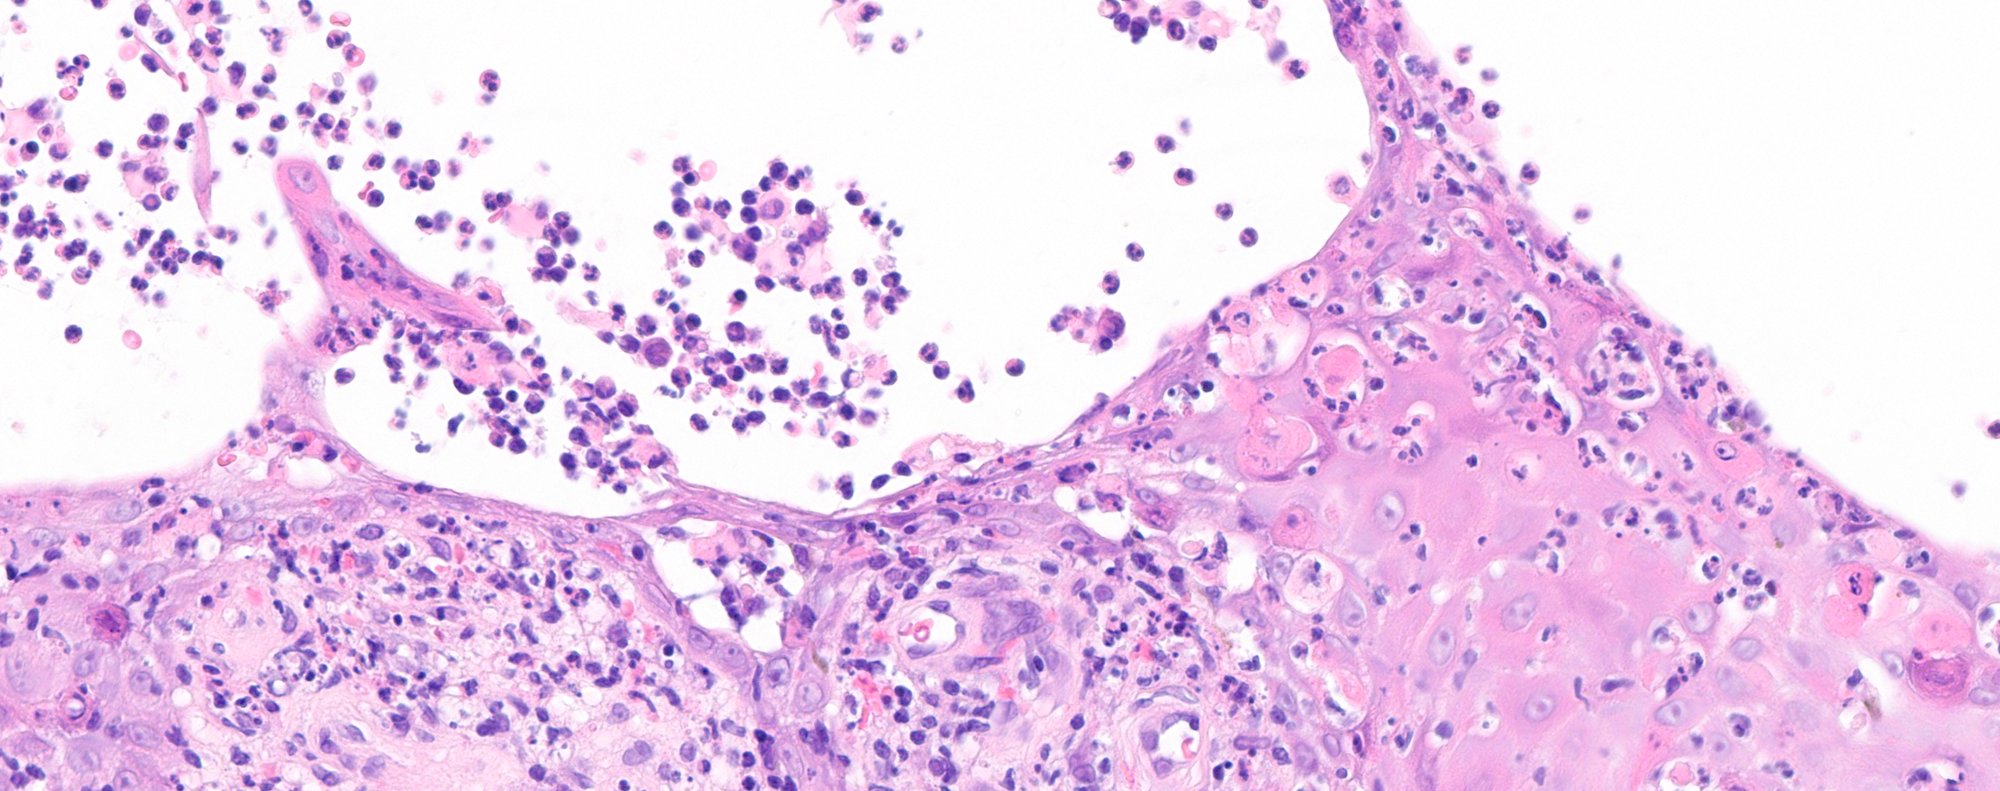

Expert microscopic examination of skin tissue serving dermatologists across Indiana and the Midwest with guaranteed 24-hour turnaround for routine cases.

Melanoma & skin cancers

Inflammatory skin diseases

Autoimmune skin disorders

Nail & hair pathology

and more...

Rapid, definitive DIF for autoimmune and inflammatory skin diseases — results guaranteed within 24 hours.